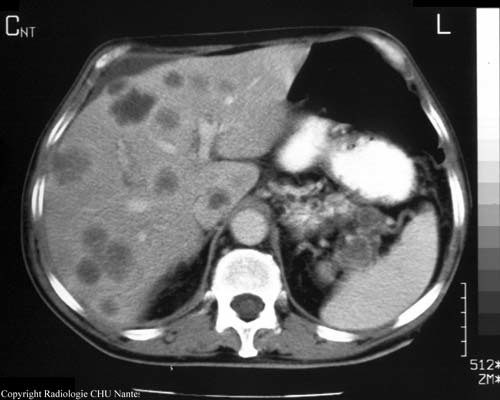

Coucou qu’est ce que c’est? (chez qqn qui a un cancer colo-rectal)

A

métastases hépatiques de cancer colo-rectal